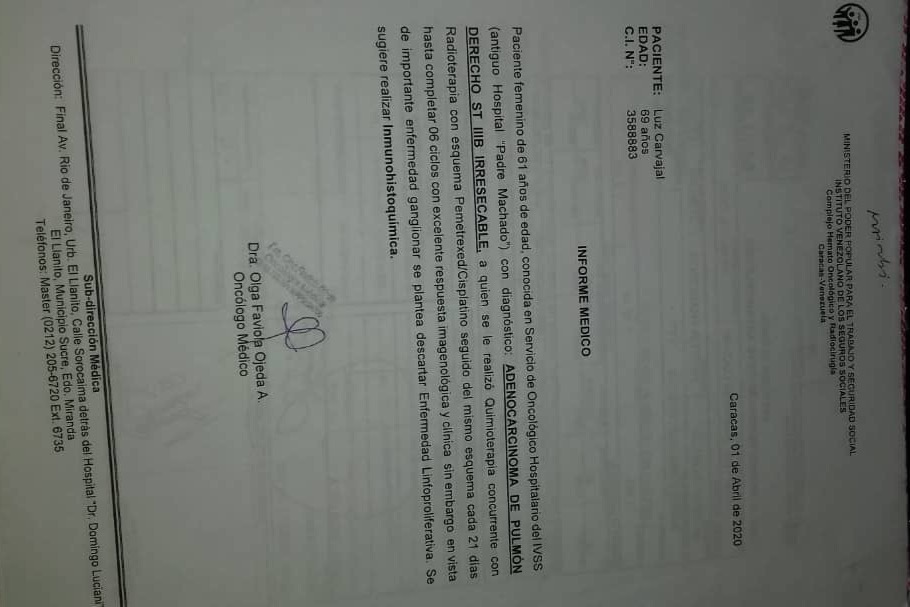

En septiembre de 2019 fue diagnosticada con cáncer de pulmón con una Lesión Ocupante de Espacio (LOE) de 2,5 cm y otra lesión en el Mediastino de 5,4 x 4,7 cm.

A través de varios familiares hemos logrado conseguir dinero para realizarle 36 ciclos de radioterapia y 6 de quimioterapia, además del tratamiento y todos los medicamentos requeridos hasta ahora, logrando una reducción importante del tamaño del tumor en pulmón en 40 %. Gracias a Dios la lesión en el mediastino se redujo también en un 80%.

Sin embargo, aún necesita varios ciclos de quimioterapia adicionales, un examen llamado PET Scan para verificar que no tiene alguna otra célula cancerígena en su cuerpo, una operación para extraer el resto del tumor, y tratamiento para acompañar todo el proceso que podría salvar su vida.

A continuación les dejo el diagnóstico, los exámenes, y los presupuestos de los próximos exámenes que hay que hacerle a mi mamá.

In September 2019, she was diagnosed with lung cancer with a Space Occupying Injury (LOE) of 2.5 cm and another lesion in the Mediastinum of 5.4 x 4.7 cm.

Through several family members we have managed to raise money to perform 36 cycles of radiotherapy and 6 of chemotherapy, in addition to the treatment and all the medications required so far, achieving a significant reduction in the size of the tumor in the lung by 40%. Thank God the injury to the mediastinum was also reduced by 80%.

However, she still needs several additional cycles of chemotherapy, a test called a PET Scan to verify that she doesn't have any other cancer cells in her body, an operation to remove the rest of the tumor, and treatment to accompany the entire process that could save her life. .

Down here I leave the diagnosis, exams, and budgets for the next exams to be done to my mom.